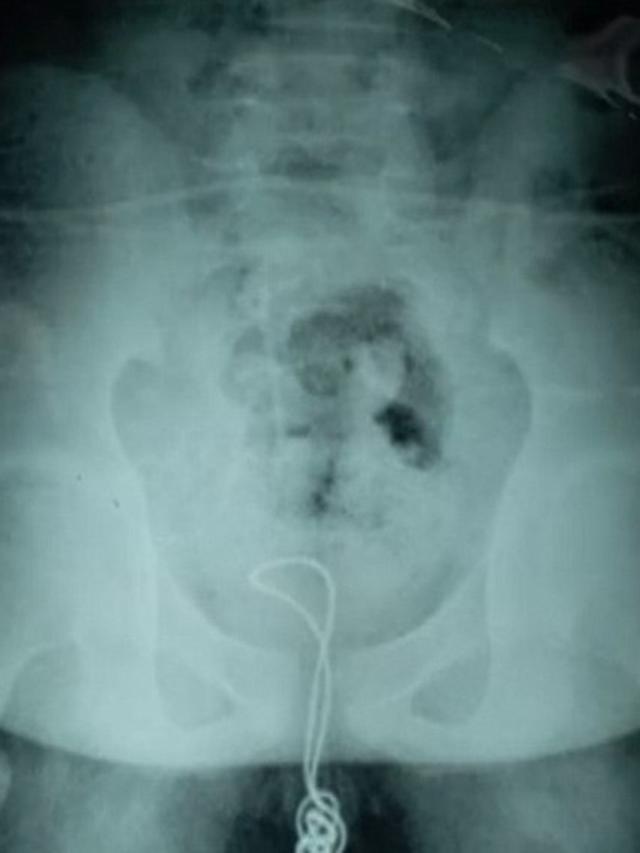

Menurut Daily Mail, para dokter di Rumah Sakit Pusat Danau yang menangani bocah itu terkejut ketika melihat kabel yang kusut di dalam kandung kemih bocah itu selama pemindaian sinar-X.

Para dokter melakukan prosedur selama satu jam dengan perlatan yang disebut cystoscope digunakan untuk mencabut kawat sepanjang 70 cm.

“Saya tidak menyangka kabel sepanjang itu dapat masuk ke uretra,” kata Dr Cai Chongyue, kepala medis yang memimpin operasi itu.

Untungnya, kawat yang berada di dalam kandung kemih itu tidak menyebabkan kerusakan serius.